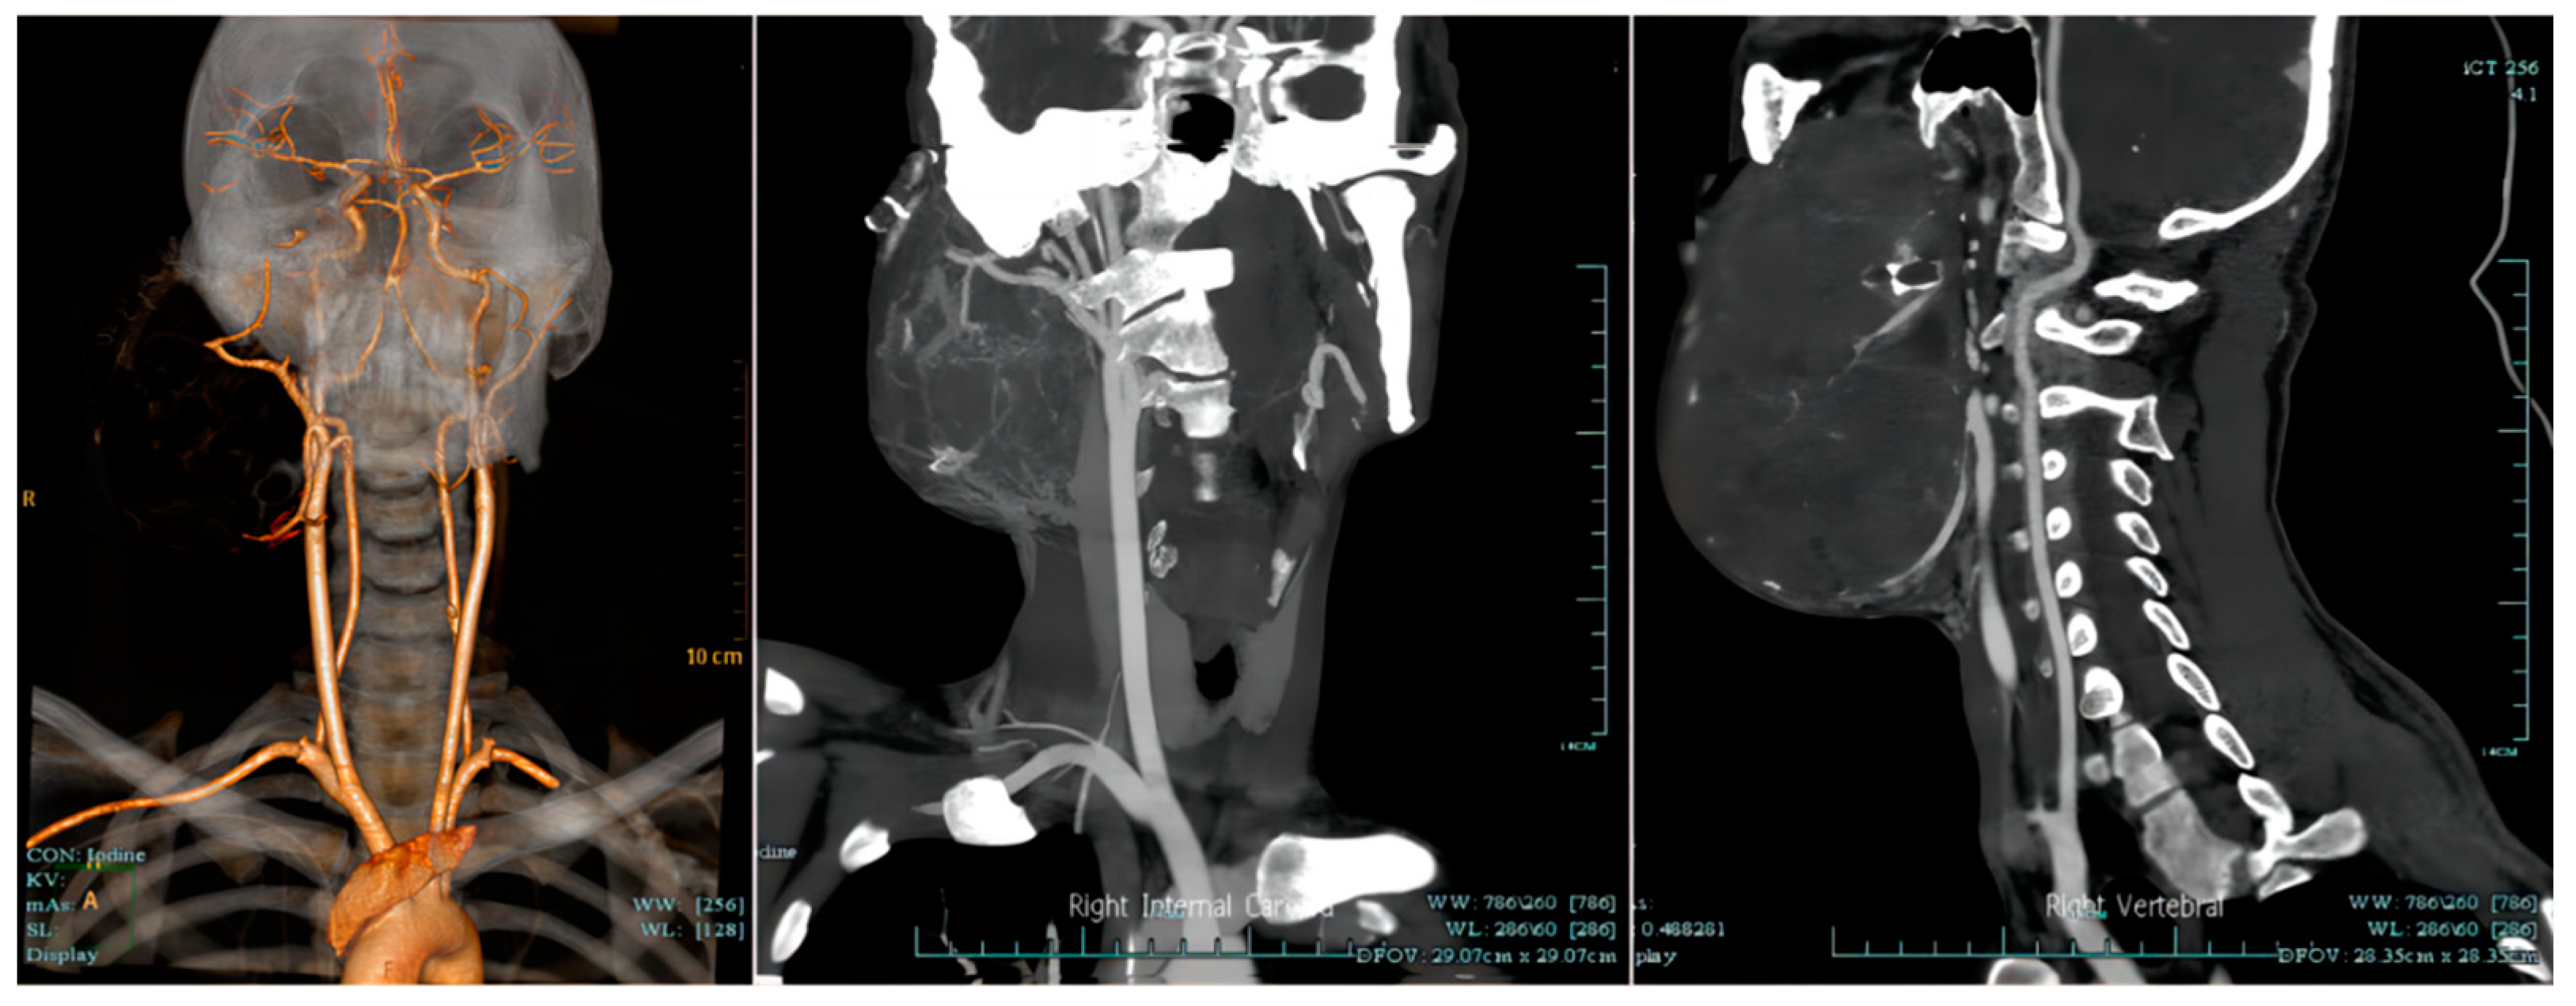

At 12 days after the interventions, multi-disciplinary experts concluded that the patient’s systemic condition was satisfactory to tolerate tumor resection (total calcium 2.77 mmol/L, creatinine 71 µmol/L, hemoglobin 91 g/L). The preoperative computerized tomography with angiography (CTA) of the neck vessels suggested that the tumor was supplied by multiple branches of the right external carotid artery (Figure 5). Thus, embolization of the right external carotid artery was performed before surgery to reduce intraoperative bleeding and the resultant surgical difficulty. The patient then underwent hemimandibulectomy to remove the diseased tissue completely. The tumor was observed to have a mix of cystic and solid components during operation, and the histopathological examination indicated this patient’s ameloblastoma was predominantly of the plexiform type, which contained a small amount of follicular structure (Figure 6). It would be difficult to tolerate one-stage surgical repair of tissue defects due to the large amount of intraoperative blood loss (>1200 mL), low intraoperative hemoglobin level (5 mg/dL), and poor coagulation status. Iodoform gauze was used as a packing material following the resection of the giant tumor. After surgery, the patient’s serum calcium and creatinine were still stabilized within the normal range (total calcium 2.34 mmol/L, creatinine 92 µmol/L), and the patient’s facial deformity, oral function, and general condition were greatly improved (Figure 7).

Figure 5.

The computerized tomography with angiography of the neck vessels suggested that the right mandibular ameloblastoma was supplied by multiple branches of the right external carotid artery.